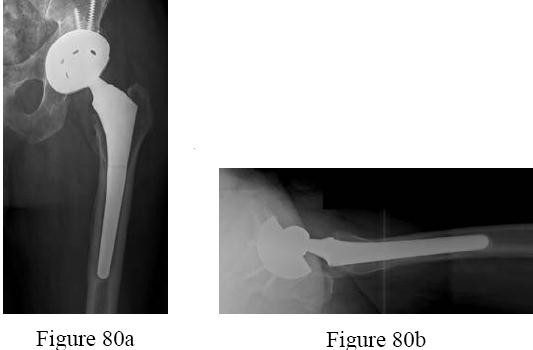

A 65-year-old woman with type 2 diabetes mellitus and hypertension who underwent an index total knee arthroplasty (TKA) 1 year ago has a knee aspirate culture positive methicillin-resistant Staphylococcus aureus periprosthetic joint infection after 2 days of increasing pain and swelling. She states her knee“never felt right.” Her erythrocyte sedimentation rate (ESR) and C-reactive protein (CRP) levels are elevated. Radiographs reveal well-fixed, appropriately positioned components.

What is the most appropriate treatment?

Explanation

This patient has had a painful knee joint since surgery, and it is possible this is a chronic infection. In this setting, a 2-stage reimplantation procedure is most appropriate. There is no role for arthroscopic debridement and resection arthroplasty is not indicated. During the second stage, it is important to obtain cultures to confirm successful eradication of the infection. If there is clinical suspicion for persistent joint infection, an intraoperative frozen section can be indicated, but gram stain is useful. Aspiration and culture prior to the intraoperative culture should be obtained after the patient has not been taking the antibiotic for a minimum of 2 weeks. ESR and CRP trends are more valuable than the actual numbers in this setting. Finally, leukocyte-labeled imaging has no role in this setting.